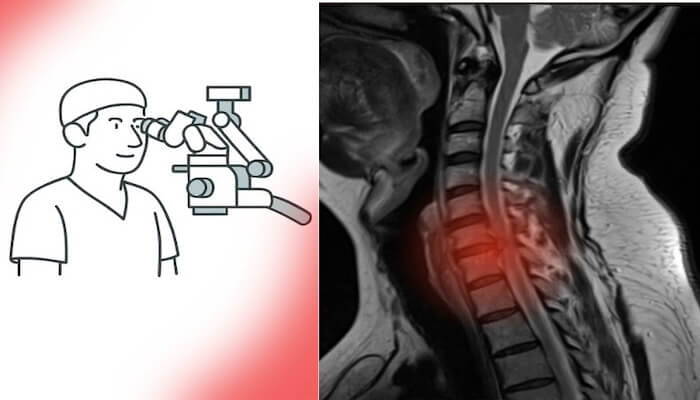

Beyin ve omurga cerrahisinde son yıllarda yaşanan teknolojik ilerlemeler, cerrahiye bakış açısını tamamen değiştirdi. Artık ameliyatlar daha küçük kesilerle, daha az kan kaybıyla ve çok daha kısa iyileşme süreleriyle gerçekleştirilebiliyor.

Mikrocerrahi, endoskopik cerrahi ve nöronavigasyon sistemleri sayesinde sinir dokuları korunarak işlem yapılabiliyor. Bu da hem cerrahi güvenliği artırıyor hem de genç hastaların ameliyat kararını kolaylaştırıyor.

Eskiden korkulan “uzun iyileşme süresi” veya “kalıcı hasar riski” gibi endişeler, yerini yüksek başarı oranlarına ve hızlı dönüş sürecine bıraktı. Özellikle bel fıtığı ameliyatı, boyun fıtığı ameliyatı ve beyin tümörü ameliyatı gibi operasyonlar artık minimal invaziv yöntemlerle çok daha kısa sürede tamamlanabiliyor.

Ameliyat mikroskopları, nöronavigasyon sistemleri, intraoperatif monitörizasyon ve endoskopik teknikler sayesinde cerrahlar artık milimetrik düzeyde güvenle çalışabiliyor. Bu da komplikasyon riskini belirgin biçimde azalttı.

Son yıllarda beyin ve omurga cerrahisinde yaşanan teknolojik devrim, ameliyatların güvenliğini ve başarısını belirgin biçimde artırdı. Mikrocerrahi, endoskopik ve minimal invaziv yaklaşımlar sayesinde artık çok daha küçük kesilerle, minimal kan kaybı ve kısa iyileşme süresiyle operasyonlar yapılabiliyor.